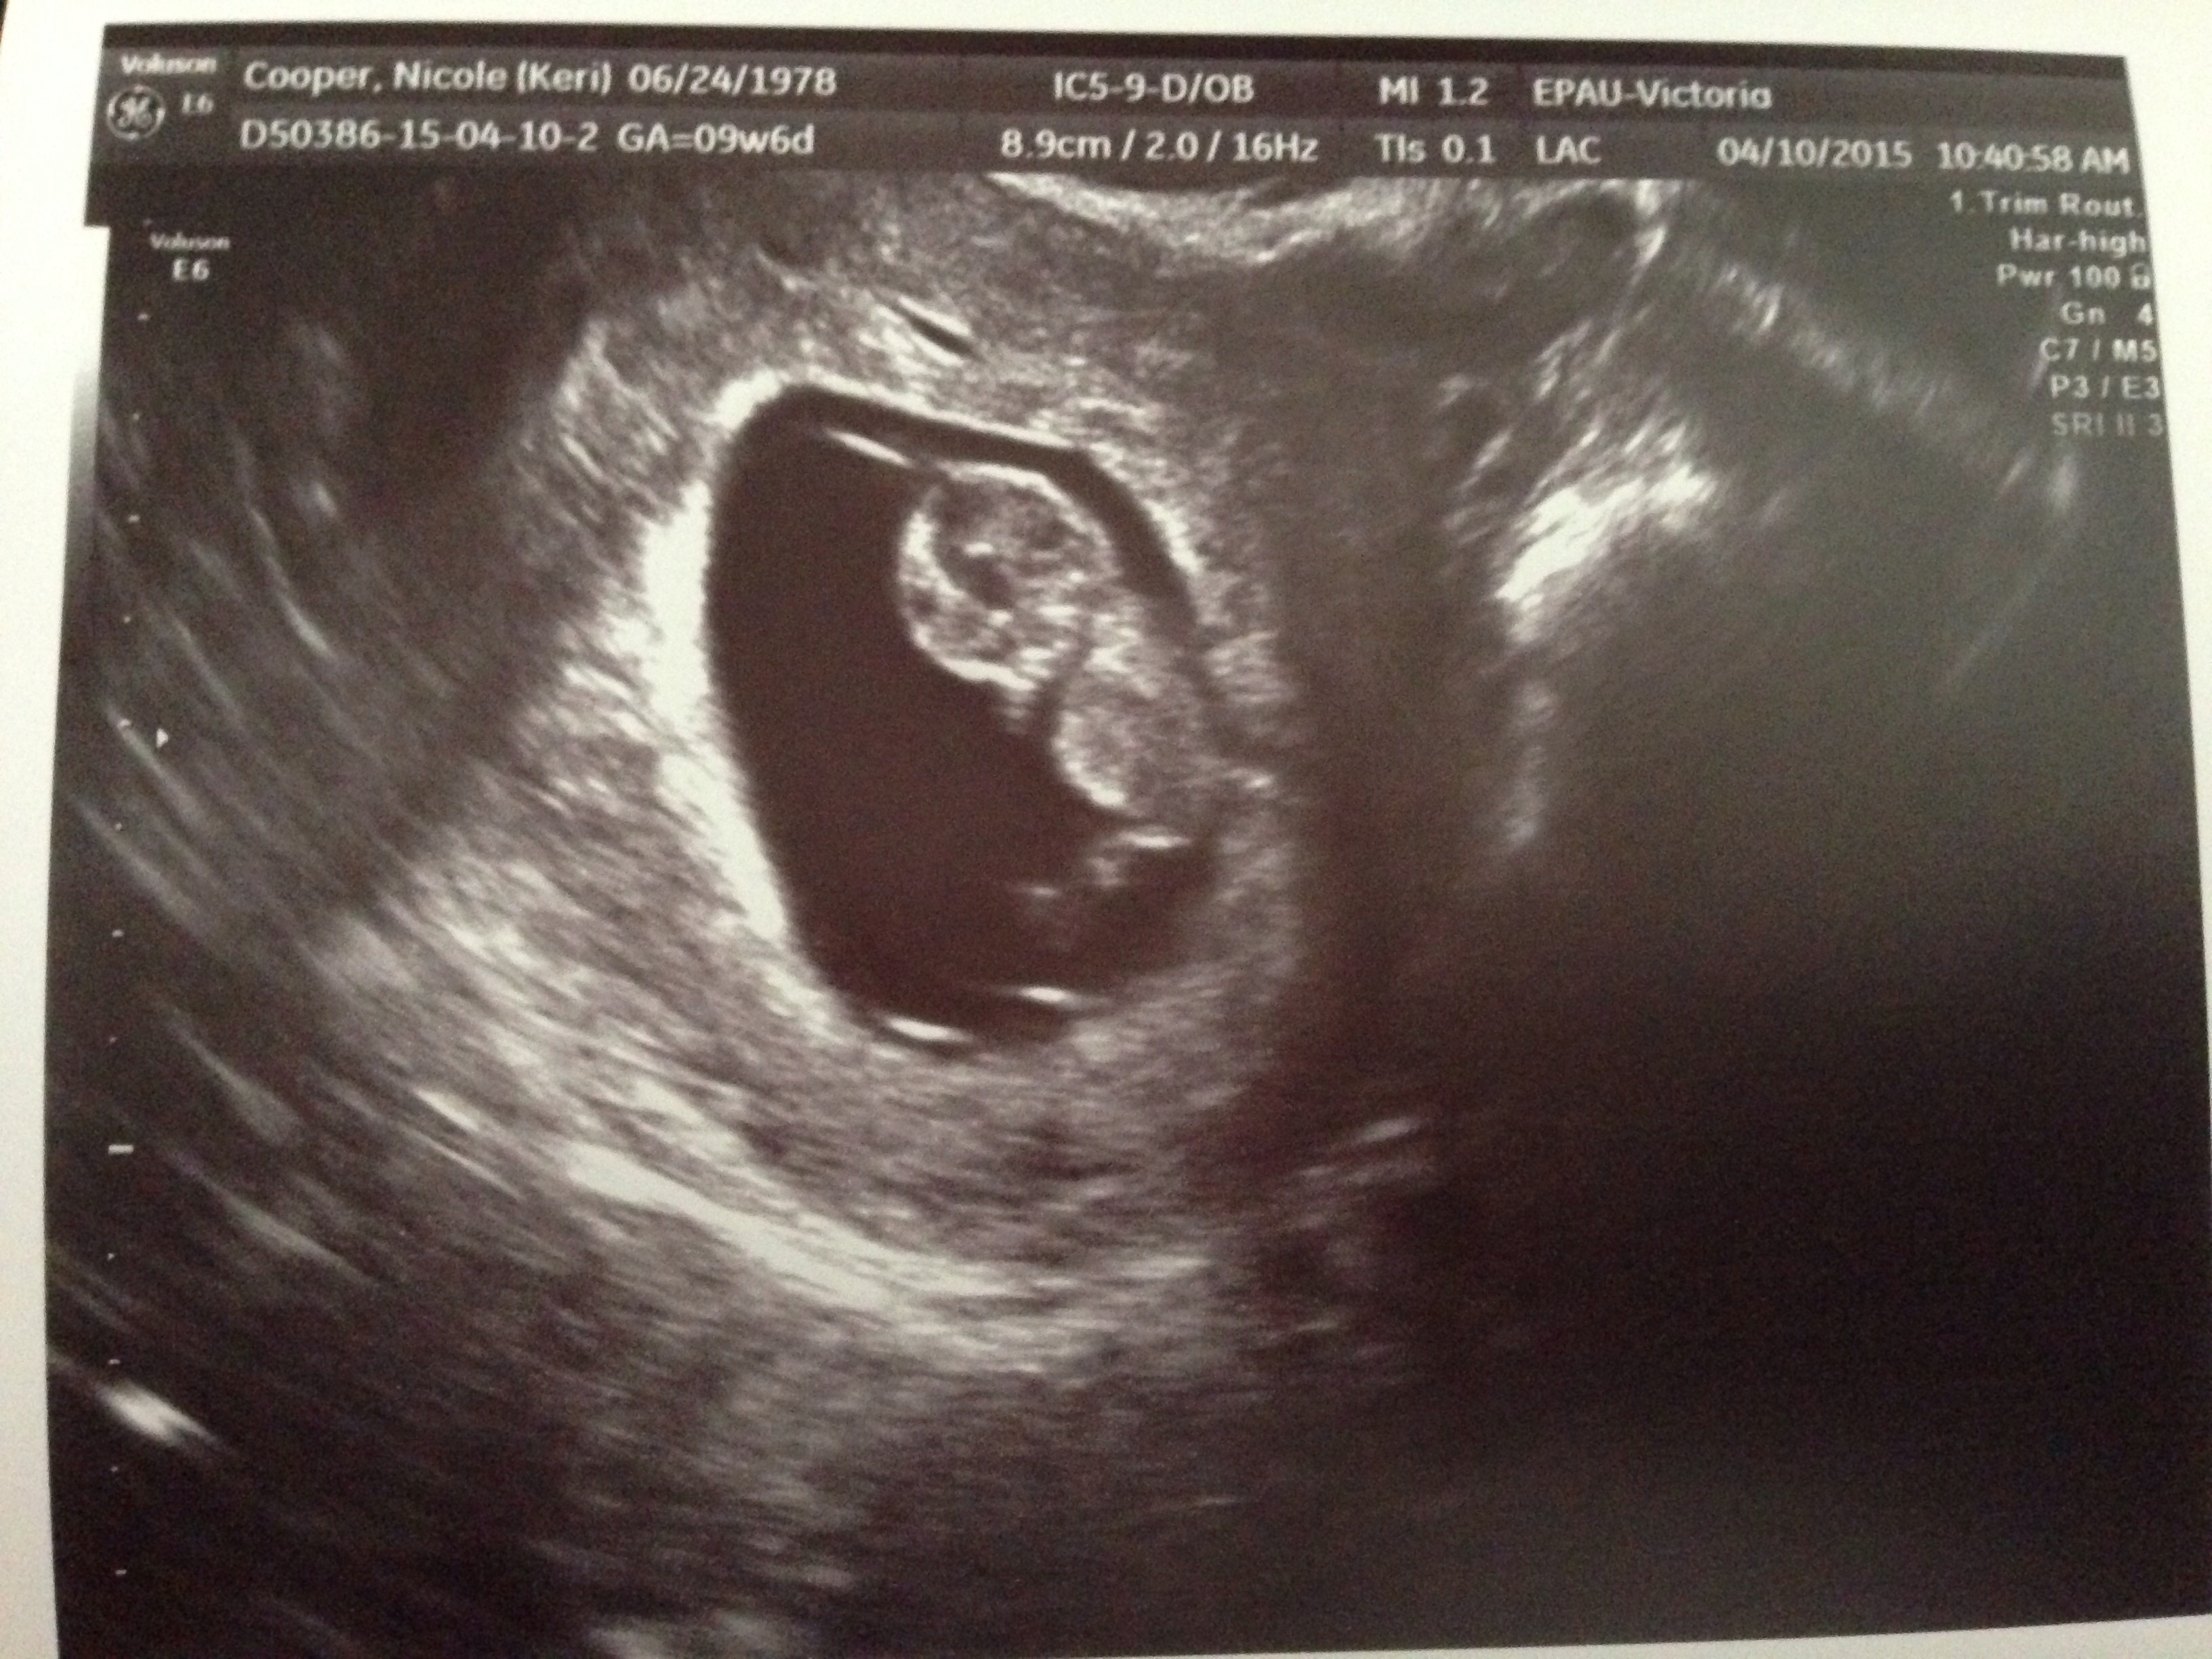

I had my first ultrasound on Wednesday when I was 9w6d. Baby was measuring at 10w3d. This picture isn't very clear because it's a picture of a picture.